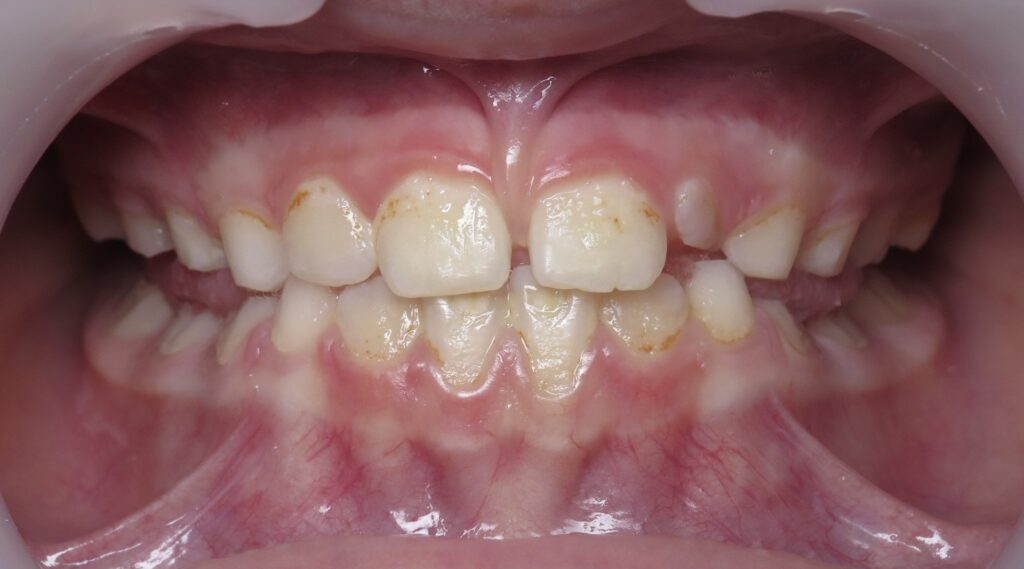

Un cas de prognathisme précoce :

Denture de lait en occlusion inversée antérieure, futur prognathe :

Photos à 6, 8 et 12 ans, puis à 16 ans après plusieurs années de fin de traitement

* Le traitement initial a été plus long pour ce cas (18 mois) en raison de la difficulté du cas.